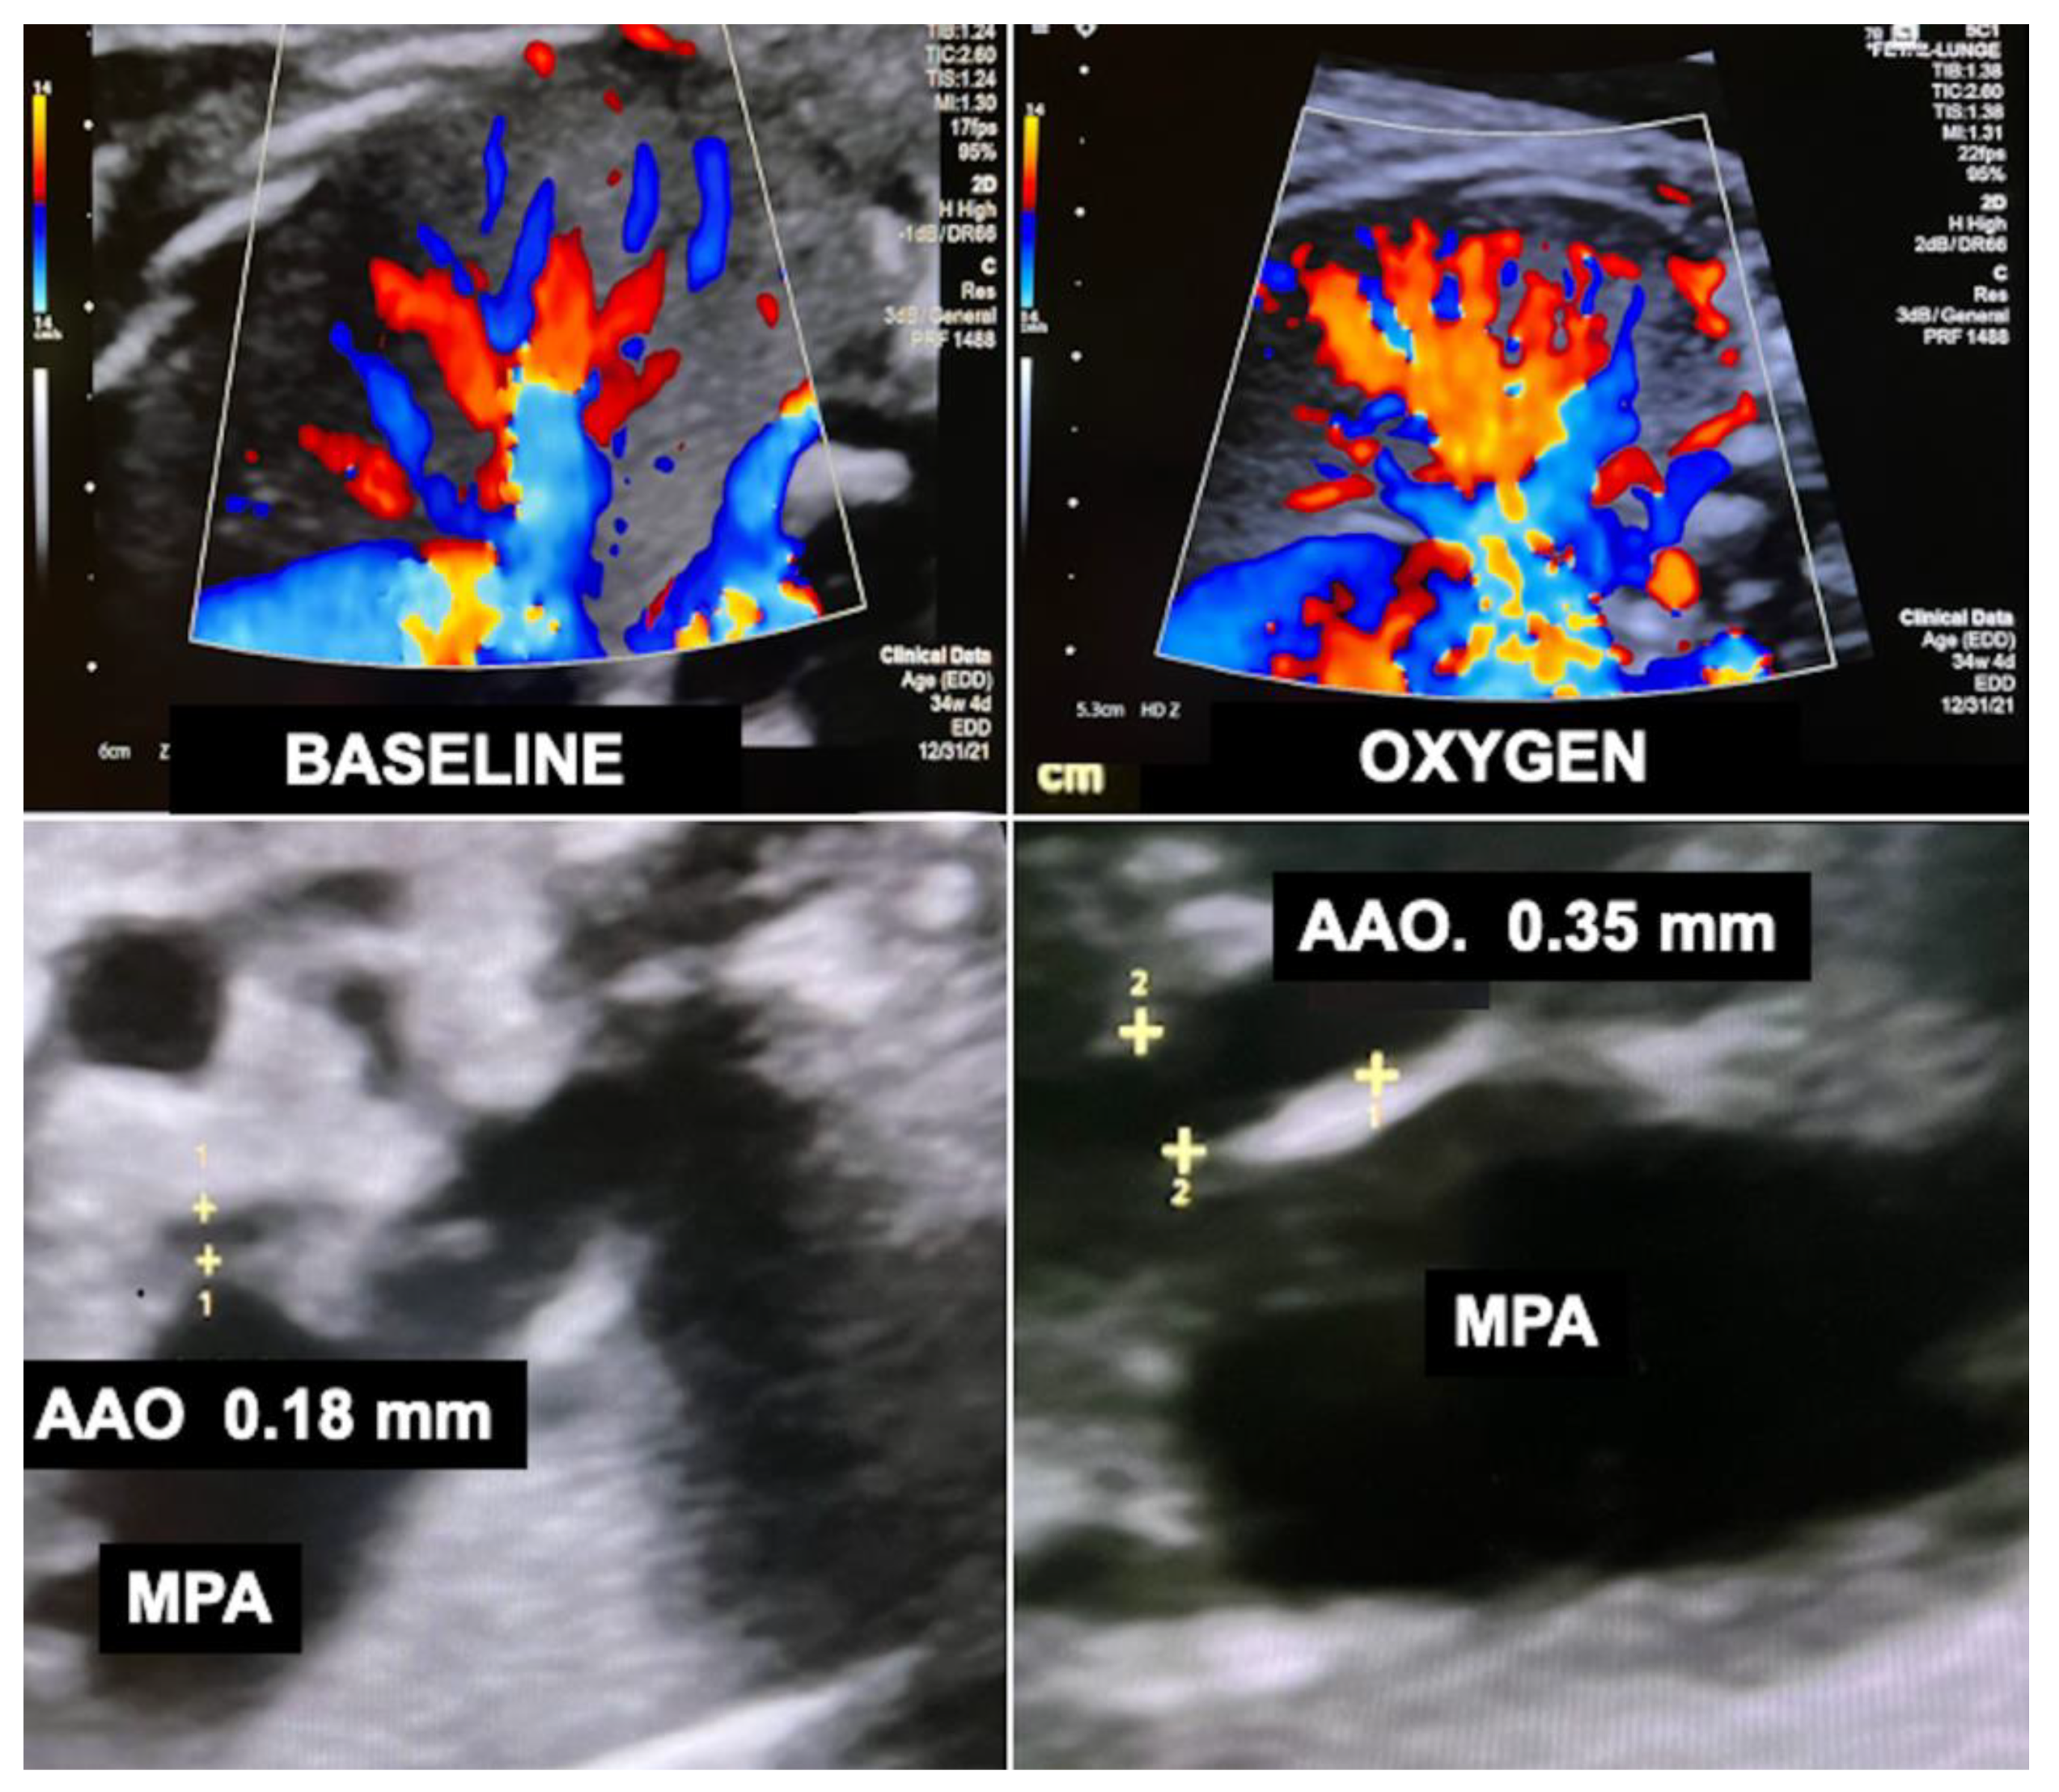

The principle is simple: A small fraction of supplemental oxygen being inhaled by pregnant women beyond 30 weeks of gestation crosses the placenta and increases the oxygen content of the fetal blood, thus inducing fetal pulmonary vasodilatation and a marked increase in lung blood flow (Figure 11). Through this mechanism, the preload from the increased pulmonary venous return challenges both hypoplastic left and right heart structures (Figure 11). Through providing 6 L/min of O2 via a face mask to the mother (approximately 35–40% oxygen) three times daily (8:00–12:00/14:00–18:00/20:00–23:00; total 10–11 h/day) from 32 + 0 to 34 + 0 weeks of gestation onwards until delivery, impressive degrees of catch-up growth can be observed in suitable cases [103].

Figure 11.

Acute loading effect of materno–fetal hyperoxygenation on the left ventricle in a fetus with hypoplastic left heart complex at 34 + 2 weeks of gestation. Top—color Doppler interrogation of a pulmonary vein before (left) and after 10 min (right) of materno–fetal hyperoxygenation demonstrates a marked increase in pulmonary flow. Bottom left—there is marked disproportion between the hypoplastic left (LV) and the dilated right ventricle (RV) before hyperoxygenation (BASELINE). Bottom right—after only 10 min of materno–fetal hyperoxygenation (OXYGEN), the left ventricle shows substantially improved filling at end diastole. Over several weeks, this effect results in catch-up growth of hypoplastic left heart structures. LA = left atrium; RA = right atrium.